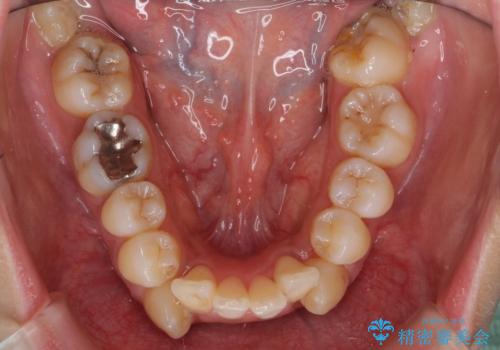

- 歯並びを気にして来院。

乳歯が残存しており、また左上の犬歯もずれて生えてきていました。

右上の前歯も細長い特殊な形をしていました。(矮小歯といいます)